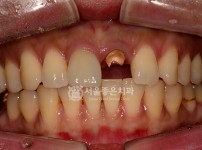

수면 지르코니아 크라운 - 앞니 신경치료 후 크라운 수복

해당 게시물은 의료법 제56조에 의거하여 로그인 후 열람이 가능합니다.

구분 보철 , 충치